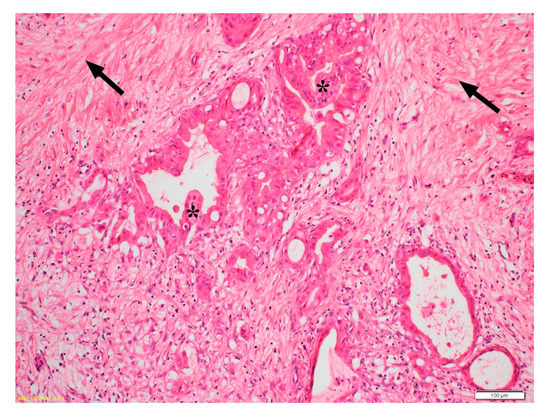

- Feig, C.; Gopinathan, A.; Neesse, A.; Chan, D.S.; Cook, N.; Tuveson, D.A. The Pancreas Cancer Microenvironment. Clin. Cancer Res. 2012, 18, 4266–4276. [Google Scholar] [CrossRef]

- Apte, M.V.; Xu, Z.; Pothula, S.; Goldstein, D.; Pirola, R.; Wilson, J. Pancreatic cancer: The microenvironment needs attention too! Pancreatology 2015, 15 (Suppl. S4), S32–S38. [Google Scholar] [CrossRef] [PubMed]

- Apte, M.V.; Park, S.; Phillips, P.A.; Santucci, N.; Goldstein, D.; Kumar, R.K.; Ramm, G.A.; Buchler, M.; Friess, H.; McCarroll, J.A.; et al. Desmoplastic reaction in pancreatic cancer: Role of pancreatic stellate cells. Pancreas 2004, 29, 179–187. [Google Scholar] [CrossRef] [PubMed]